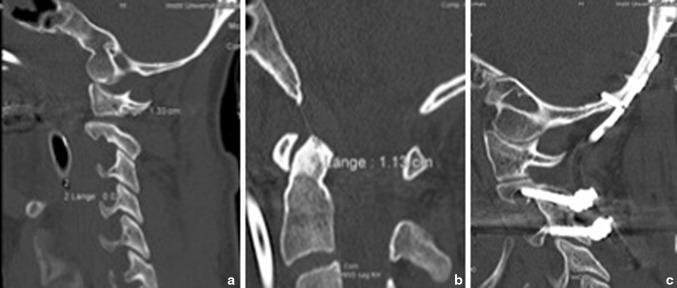

Four patients sustained high-energy injuries in a motor vehicle accident, and one patient fell from a tree, and the average injury severity score (ISS) was 44.4 points. All five patients (100 %) with AOD were primarily diagnosed, and a Halo fixator was initially used for treatment in four out of five cases. Only one patient (patient #2) was primarily treated by means of occipito-cervical stabilisation using an internal fixator. On day 11 and 3 (post-trauma), respectively, the Halo fixator of patient #1 and #3 was removed and secondary occipito-cervical stabilisation was conducted. In one case (#1), postoperative CT scan documented unilateral C2 pedicle screw misplacement into the vertebral artery foramen (Fig. 1c), but without neurological deterioration. Therefore we performed no revision. After surgical treatment, patients received a soft collar for 6 weeks, no one received Halo vest again. Three out of five patients (60 %) died on day 2, 7 and 11, respectively, post-trauma due to the severity of their secondary traumatic brain injuries. Additional empirical data of the five patients can be found in Table 2. These data show clearly better radiological parameters (BDI, BAI, powers ratio, and pang rule) for both of the surviving adult patients (patient #1 and #2) compared to the two adult deceased patients (patient #3 and #4). The X-line was pathologic in all five cases, including the child (patient #5). Furthermore, the initial GCS showed clearly lower scores for all three died patients.

Fig. 1.

a Sagittal CT image: Pat. #1, AOD with anterior dislocation. b Sagittal CT image: Pat. #1, AOD with BDI measurement of 11 mm. c Sagittal CT image: Pat. #1, 1 year after occipito-cervical internal fixator from C0 to C2/3. CT scan documented asymptomatic unilateral misplacement of pedicle screw into the vertebral artery foramen

One patient (#1) (Fig. 1a, b, c) was unfit for work, but still able to walk and live alone. Due to the patient’s young age, the occipito-cervical implant was removed 22 months post-surgery. There were no radiological or clinical signs of instability following this procedure, but the mobility of the cervical spine was considerably improved.